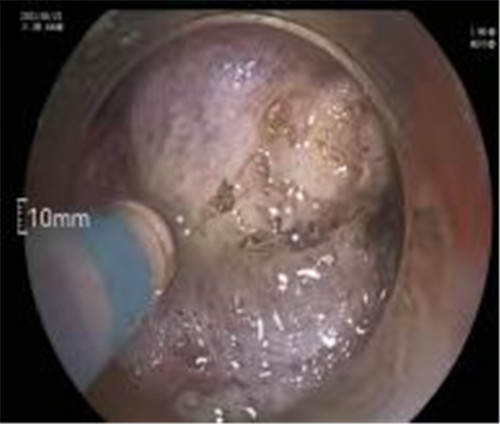

近期病例之一,圖片依次為:胃鏡、超聲胃鏡、ESE術(shù)中、術(shù)后、切下病變。

通過內(nèi)鏡切開瘤體表面粘膜,分離后挖除瘤體,或以消化道全層切除的方法切除瘤體,并在內(nèi)鏡下縫合切口。與傳統(tǒng)手術(shù)相比,該項(xiàng)技術(shù)利用了人體自然通道,不會(huì)破壞人體結(jié)構(gòu),更加微創(chuàng)。不超過3cm向消化道腔內(nèi)生長(zhǎng)為主的良性或低度惡性粘膜下腫瘤(如間質(zhì)瘤、類癌、平滑肌瘤等),都可采用ESE治療。